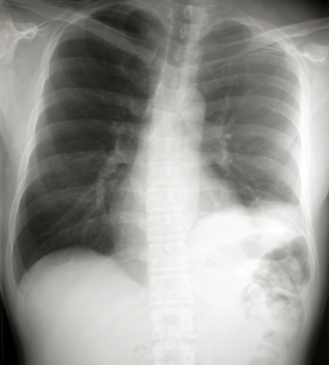

ДИАГНОСТИКА

Диагноз устанавливается после осмотра больного, лабораторных и инструментальных исследований. Проводятся: клинический анализ крови, рентгенография грудной клетки, КТ грудной клетки, по показаниям бронхоскопия, исследование мокроты (микроскопия и бактериологическое исследование), исследование крови на стерильность (гемокультура), пульсоксиметрия (количество кислорода в крови)